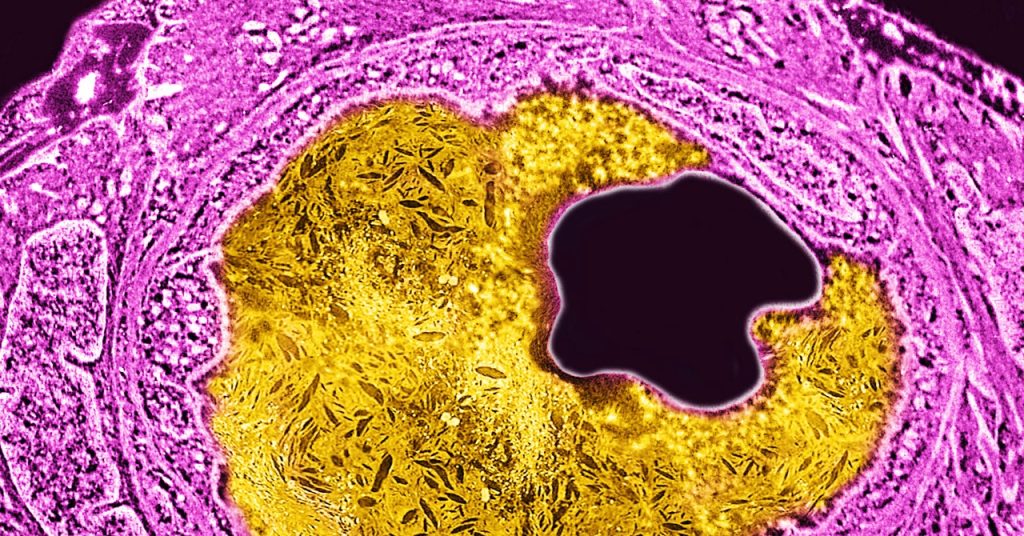

وفي اختبار أولي صغير على البشر، أظهر الباحثون أن حقنة واحدة من علاج جديد لتحرير الجينات يمكن أن تقلل من نسبة الكولسترول، وهي المادة الدهنية التي تسد الشرايين وتصلبها مع مرور الوقت.

ويهدف علاج تحرير الجينات إلى خفض نسبة الكوليسترول بشكل دائم باستخدام تقنية كريسبر لتحرير جين في الكبد. أعطى الباحثون حقنة واحدة، بجرعات مختلفة، للمرضى الذين كان متوسط أعمارهم 54 عامًا. في حين أن الجرعات المنخفضة لم يكن لها تأثير كبير، فإن الجرعة الأعلى خفضت نسبة الكوليسترول الضار LDL بنسبة 55 بالمائة في المريض الوحيد الذي تناولها. وفي الوقت نفسه، شهد مريضان حصلا على الجرعة التالية الأعلى انخفاضًا بنسبة 39% و48%.

يستخدم العلاج شكلاً أحدث وأكثر دقة من Crispr يسمى التحرير الأساسي لتعطيل جين في الكبد يسمى PCSK9. يلعب هذا الجين دورًا حاسمًا في التحكم في نسبة الكوليسترول الضار في الدم. فبدلاً من قطع الجينات، كما تم تصميم تقنية Crispr للقيام بذلك، يقوم تحرير القاعدة ببساطة بتبديل حرف DNA بحرف آخر. تم تصميم علاج Verve لتغيير الحرف A إلى الحرف G، والذي يحول بشكل فعال PCSK9 الجينات قبالة.